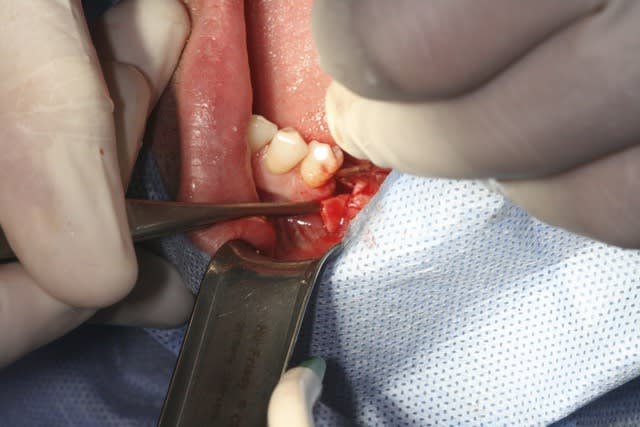

image1: incision verticale + décollement du lambeau de proche en proche

Désolé pour la qualité, c'est tout ce que j'ai..

Ram1 cdupuy - Eugenol